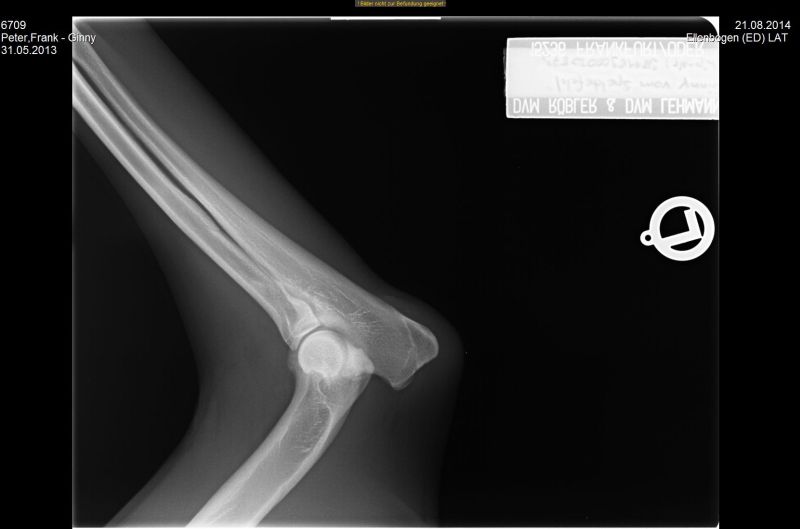

21.08.2014 - Ginny HD-und ED geröntgt - 15 Monate alt